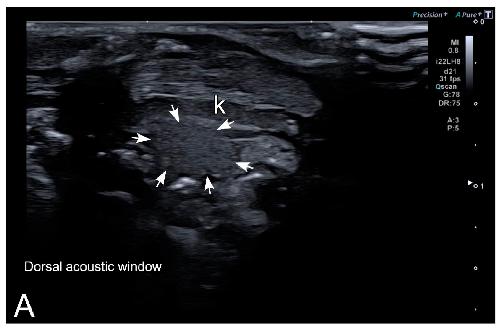

Sex Determination in Two Species of Anuran Amphibians by Magnetic Resonance Imaging and Ultrasound Techniques., Ruiz-Fernández MJ, Jiménez S, Fernández-Valle E, García-Real MI, Castejón D, Moreno N, Ardiaca M, Montesinos A, Ariza S, González-Soriano J., Animals (Basel). November 18, 2020; 10 (11):